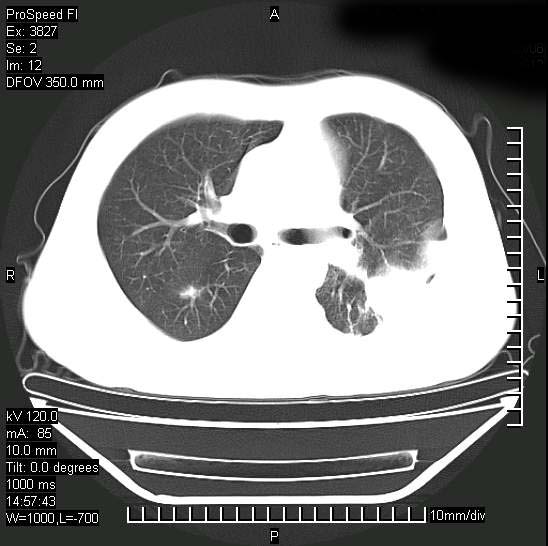

男性,一月前出现右侧肋区疼痛,较剧烈,干咳,无发热,自诉使用抗炎药后缓解,几天前又出现左侧剧烈疼痛,

发热,体温38。9,今天ct,考虑左侧包裹性脓胸,胸腔积液,右上中肺小斑片影,结核/炎症?胸水未见恶性细胞。